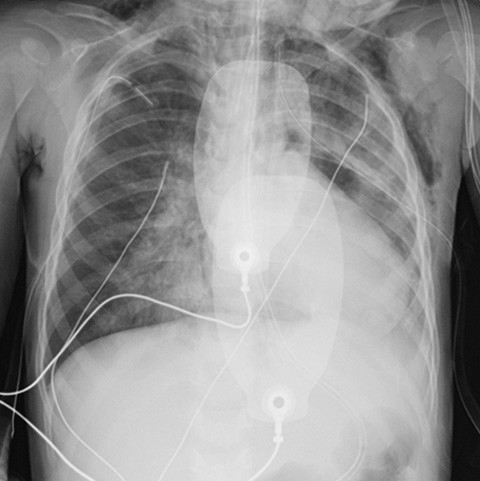

Det ble gitt 48 mg intravenøs hydrokortison og hyppigere inhalasjoner med NaCl og salbutamol i samme dose som tidligere. Kapillær blodgassundersøkelse viste på dette tidspunktet pH 7,29 og pCO2 6,7 kPa. Barnet ble flyttet til intensivavdelingen. Det ble bemerket hevelse på halsen. Nytt røntgen toraks viste pneumomediastinum og bløtdelsemfysem på halsen og venstre side av toraks.

I påvente av teamets ankomst ble det gitt inhalert 20 ppm nitrogenmonoksid (1). Det ble også gitt ny inhalasjon med 2,5 mg salbutamol samt intravenøs 120 mg aminofyllin og 625 mg magnesiumsulfat, uten at man så bedring hos pasienten. Sirkulatorisk holdt barnet seg stabilt med 0,1 µg/kg/min adrenalininfusjon, men det forelå et livstruende ventilasjonsproblem. Det ble besluttet å legge toraksdren bilateralt på vital indikasjon, da man hørte minimale respirasjonslyder og klinisk og røntgenologisk økende emfysem. Påfølgende kontroll med røntgen toraks viste økende fortetninger, pneumomediastinum og emfysem (figur 2). Antibiotikabehandlingen ble endret til kombinasjonen 625 mg cefotaksim og 120 mg klindamycin intravenøst.